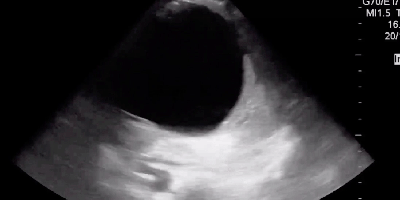

Make the POCUS diagnosis, sono of the week, Sono Stuff